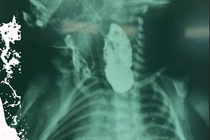

Bệnh nhân nuốt răng giả trong lúc ăn, được xử lý kịp thời tại bệnh viện, đảm bảo an toàn và không biến chứng.

Bệnh nhân mắc dị vật dài 12 cm trong thực quản đã được xử lý nhanh chóng, phòng tránh các biến chứng nguy hiểm nhờ kỹ thuật nội soi hiện đại.